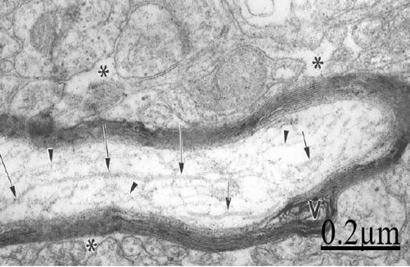

Brain trauma, brain aging and degenerated myelinated axons

At the level of neuropil we found myelinated axonal degeneration (Figures 17&18).30 The longitudinal ultrathin sections of degenerated myelinated axons show the vacuolated myelin sheath and disruption of cytoskeletal structures (Figure 19).

Figure 18 Brain traumas, subdural hematoma. Electron microscopy of a longitudinally section of a degenerated myelinated axon exhibiting fragmented microtubules (arrows) and microfilaments (arrowheads). Note the vacuolated myelin sheath (V) and the enlarged neighboring extracellular space (asterisks).